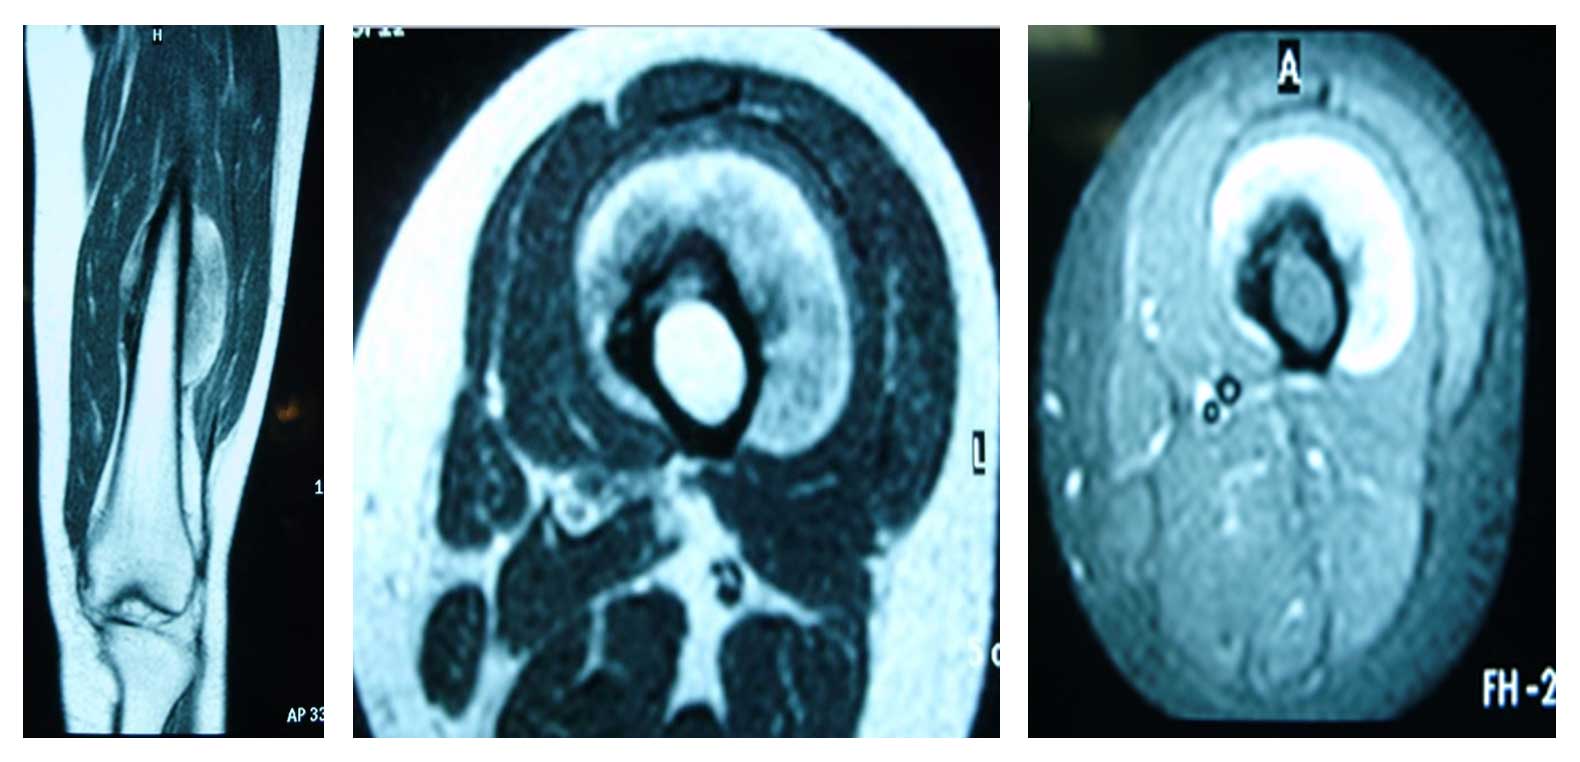

Ameliyat Öncesi: MR’da femur diafiz anterior yüzeyden kaynaklanan düzenli sınırlı tümör dokusu görülmekte.